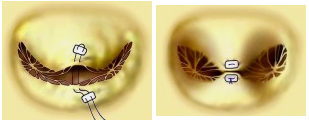

Lembi valvolari mitralici con i 3 scallops (A1, P1 - A2, P2 - A3, P3), delle due commissure e della continuità mitro-aortica.